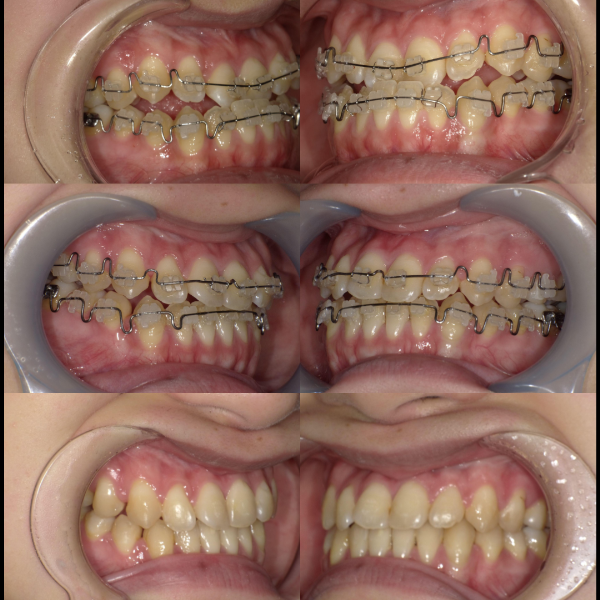

現在、歯列不正になる原因は、下顎の位置関係、歯の傾きなど様々な要因があることがわかっています。

そういった様々な要因を取り除くことで、従来、小臼歯(4番、5番)を抜歯しなければ治療できない症例でも、非抜歯で治療可能となってきているのです。

機能的に小臼歯は非常に大切な歯であることから、最大限小臼歯を抜歯せずに治療できる治療方針を考えます。

また、下顎の位置関係、歯の傾きなどの原因を新素材ゴムメタルワイヤーで治療を行うことでほとんどの症例で小臼歯を抜歯しなくても治療可能になってきています。